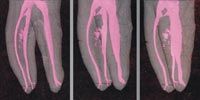

FIGs. 3–4 The roots on this radiograph have been colored to highlight the variety of irregular canal anatomies that are commonly found (Fig. 3, above). Teeth-such as this one with five-can have unusual numbers of canals. (Fig. 4, below).

Anatomic anomalies and variations in the root canal shapes and space and occasionally pulp stones (Fig. 2) are identifiable on radiographs and CBCT scans. That said, canals are infrequently as straight as they may appear on a radiograph. They tend to be oval and irregular rather than round and regular, and typically present with a variety of curvatures, including deltas and bayonet shapes (Fig. 3) making instrumentation more challenging. An additional mesiobuccal canal is seen in Fig. 4, a mesial-angled radiograph of a mandibular molar with 5 canals.